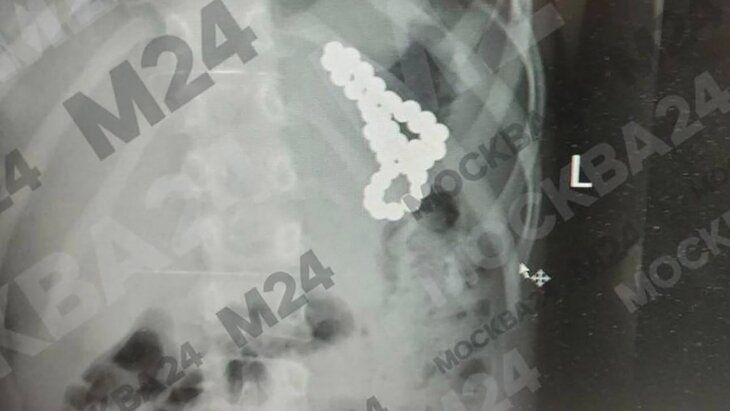

Московские врачи спасли младенца, проглотившего ключ-скрепку от сим-карты

18 февраля 2025

Московские хирурги спасли школьницу, проглотившую 46 магнитных шариков